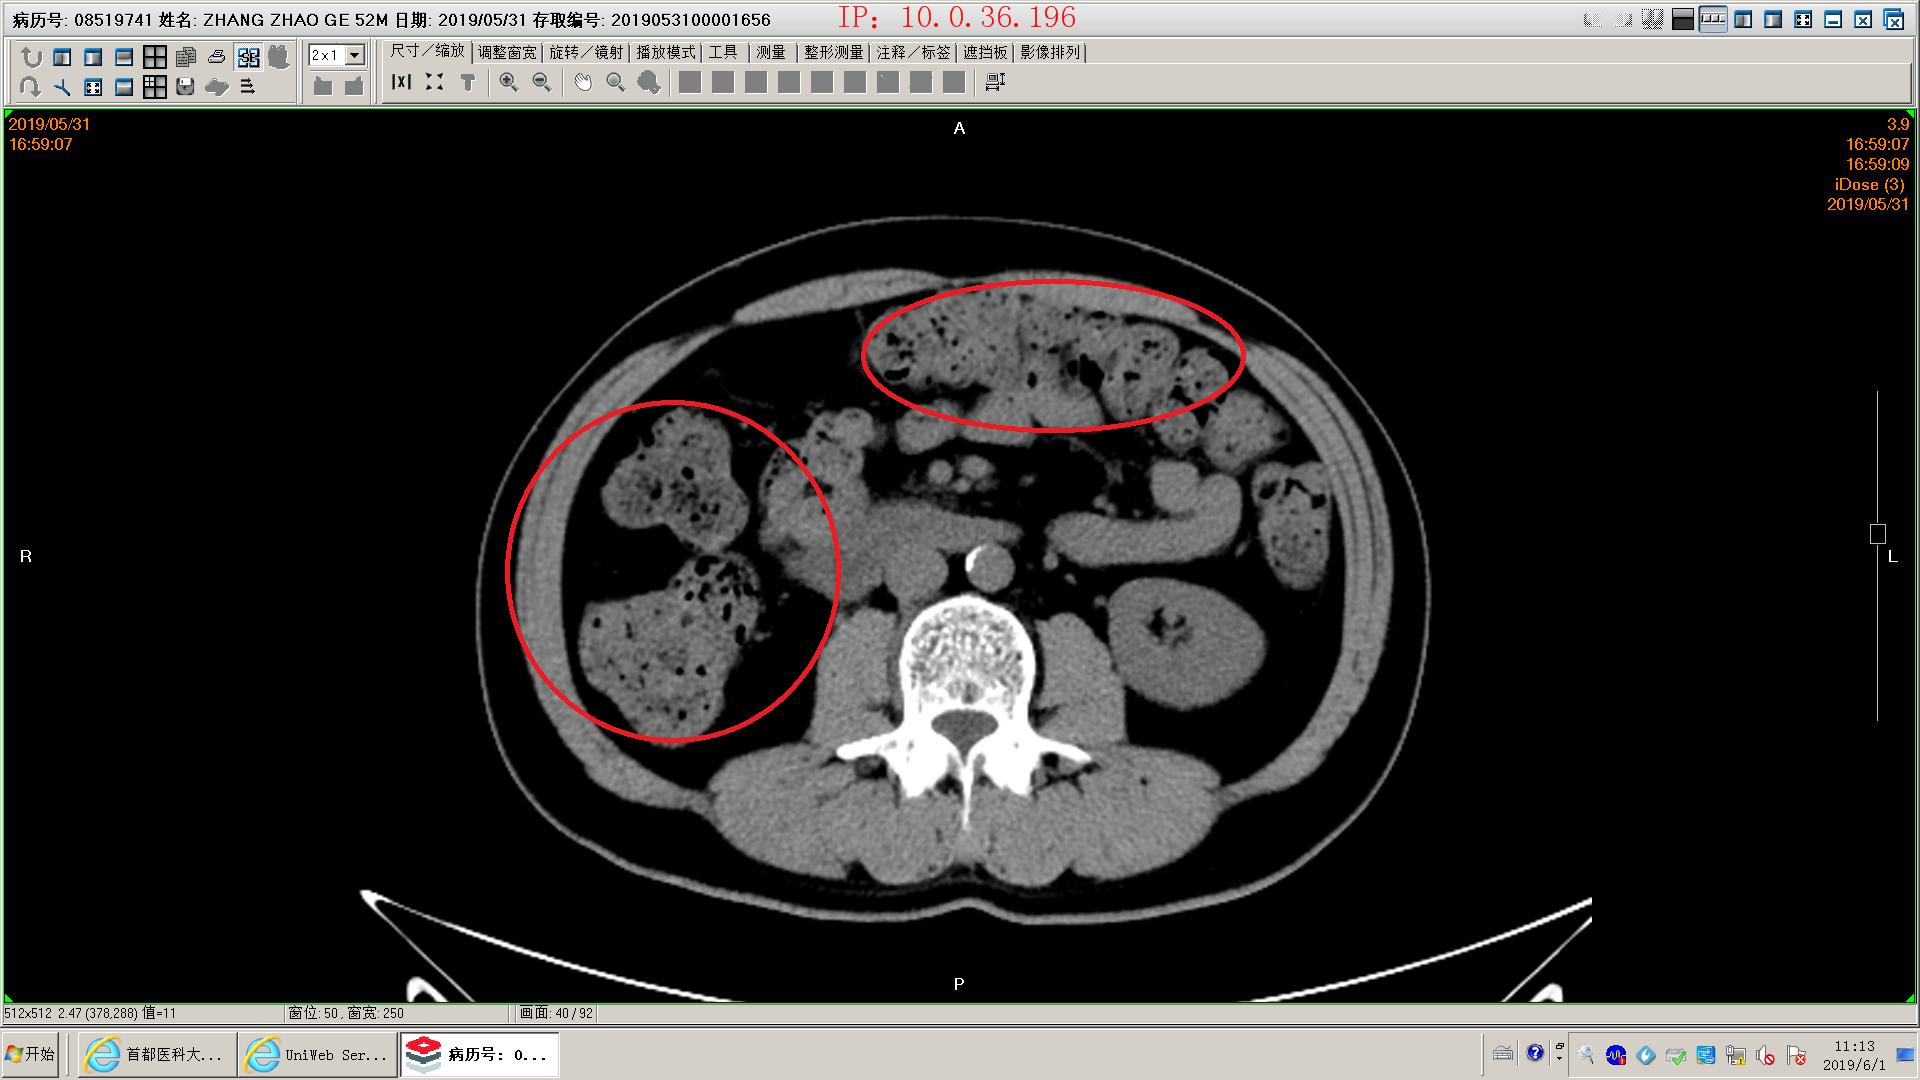

下面是一例胆源性胰腺炎影像学和化验表现,这个病人没有脏器功能不全,胰腺坏死不明显,周围没有明显积液,还不是重症胰腺炎。虽然有可疑胆管结石,但是没有黄疸,我们会在做核磁mrcp证实一下结石的位置。患者胃里面有一些残存的食物,我们会用胃管做胃肠减压,有助于胃肠道休息恢复;肠道里面积存的粪便也比较多,肠鸣音听不到,通过肥皂水灌肠促进肠道蠕动排除,有助于胃肠道功能恢复。然后给予生长抑素抑制胰酶分泌,禁食水补液,消炎治疗。

肠道积存大量粪便